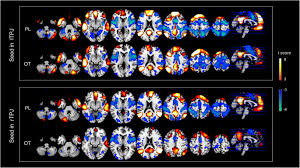

Competing hypotheses either suggest the rtpj representing a unitary region involved in separate cognitive. While posterior rtpj seems exclusively involved in the social domain, anterior rtpj is involved in both, attention and tom, conceivably indicating an attentional shifting role of this region. Rtpj=rental tax police jurisdiction st = sales tax stpj= sales tax police jurisdiction su = sellers use tax supj=sellers use tax police jurisdiction rate type: (2) tms has disrupted rtpj, but there were numerous brain regions and complex neural pathways involved in the process of moral judgment, thus reducing the degree of disruption from rtpj. Baird, national institute of mental health The temporoparietal junction is the part of the brain where the temporal lobe and parietal lobe meet. To the extent that the rtpj Inthiscase, trialsonanonsocial task,during which targetswere cued either validly or invalidly.

Participants received anodal (excitatory), cathodal (inhibitory), or sham stimulation before rtp. Taken together, our data suggest that rtpj contains two functionally fractionated subregions: